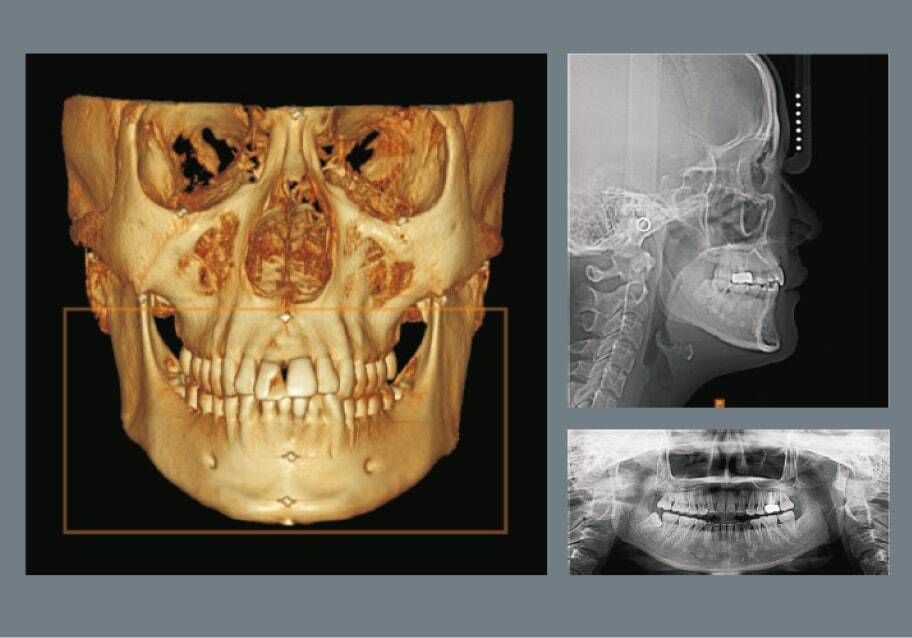

КТ челюсти применяется для диагностики сложных случаев: имплантации зубов, лечения корневых каналов, выявления кист, переломов и аномалий челюсти. Она позволяет планировать операции с точностью до миллиметра, снижая риски осложнений на 30–50%. В России КТ востребована в городских клиниках и сельских районах, где бюджет на лечение ограничен (от 3000 руб. за исследование), экономя на дорогостоящих ошибках. Подходит для семей: безопасна для детей при низкой дозе облучения; для бизнеса — повышает эффективность стоматологических услуг. Учитывайте нормы СанПиН 2.6.1.1192-03: доза не более 100 мкЗв/год; КТ интегрируется с ПО для моделирования.

Особенности КТ включают использование конусно-лучевой томографии (CBCT) для стоматологии, которая дает 3D-изображения за 10–30 секунд с разрешением 0.1–0.4 мм. Процесс: пациент сидит неподвижно, аппарат вращается вокруг головы; данные обрабатываются за минуты. В России оборудование сертифицировано по ГОСТ Р 50444-92, с антикоррозийной защитой и УФ-фильтрами. Преимущества: точность в 95% случаев, минимизация облучения (0.1–0.5 мЗв); минусы — высокая стоимость аппарата (от 5 млн руб.) и необходимость в обучении персонала. Популярные модели: Carestream, Vatech; экологичны, но требуют утилизации. В быту — простота для пациентов, без подготовки.